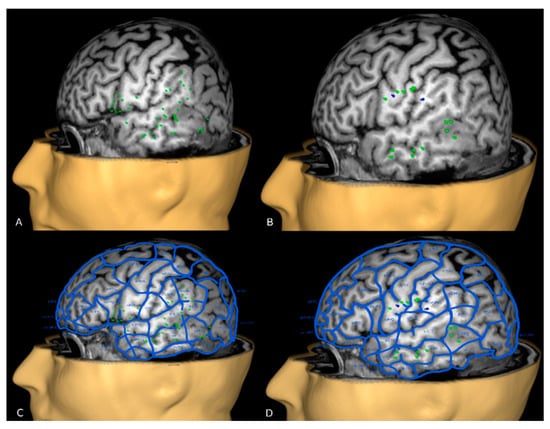

2.5. nTMS Language Cortical Mapping and Off-Line Analysis

2.6. nTMS Based DTI-FT of Language Pathway

2.7. Presurgical Planning